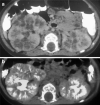

ARPKD/CHF is an inherited disease characterized by non-obstructive fusiform dilatation of the renal collecting ducts leading to enlarged spongiform kidneys and ductal plate malformation of the liver resulting in congenital hepatic fibrosis. ARPKD/CHF has a broad spectrum of clinical presentations involving the kidney and liver. Imaging plays an important role in the diagnosis and follow-up of ARPKD/CHF. Combined use of conventional and high-resolution US with MR cholangiography in ARPKD/CHF patients allows detailed definition of the extent of kidney and hepatobiliary manifestations without requiring ionizing radiation and contrast agents.